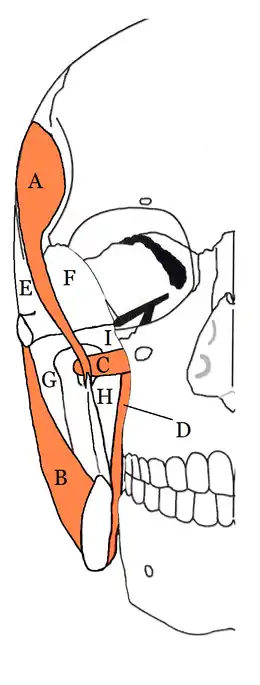

This term is sometimes used, and is a collective name for the submasseteric (masseteric), pterygomandibular, superficial temporal and deep temporal spaces. The infratemporal space is the inferior portion of the deep temporal space. The superficial temporal and the deep temporal spaces are sometimes together called the temporal spaces. The masticator spaces are paired structures on either side of the head. The muscles of mastication are enclosed in a layer of fascia, formed by cervical fascia ascending from the neck which divides at the inferior border of the mandible to envelope the area. Each masticator space also contains the sections of the mandibular division of the trigeminal nerve and the internal maxillary artery.[4]

The masticator space could therefore be described as a potential space with four separate compartments. Infections usually only occupy one of these compartments, but severe or long standing infections can spread to involve the entire masticator space.[7] The compartments of the masticator space are located on either side of the mandibular ramus and on either side of the temporalis muscle.

Submasseteric space

This is also referred to as the masseter space or the superifical masticator space. The submasseteric space is logically located under (deep to) the masseter muscle, created by the insertions of masseter onto the lateral surface of the mandibular ramus. Submasseteric abscesses are rare and are associated with marked trismus.

Pterygomandibular space

The pterygomandibular space lies between the medial side of the ramus of the mandible and the lateral surface of the medial pterygoid muscle.

Deep temporal space (infra-temporal space)

The infra-temporal space is the inferior portion of the deep temporal space.[7]